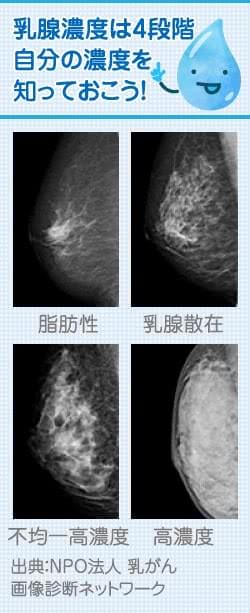

高濃度乳腺 デンスブレストって 医療法人創起会 くまもと森都総合病院

高濃度乳房とは 要因や画像や授乳との関係を調査 こんな人は注意